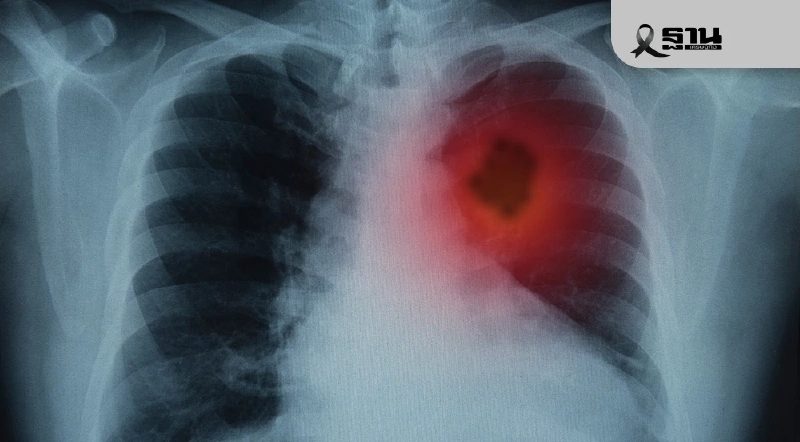

ตระหนักรู้เรื่อง “ปอด” การผ่าตัดทรวงอกรักษาโรคสำหรับผู้ป่วย

- การผ่าตัดปอดและทรวงอกในไทยได้พัฒนาสู่มาตรฐานสากล โดยเน้นเทคนิคการผ่าตัดส่องกล้อง (Minimally Invasive Surgery) มากขึ้น

- โรงพยาบาลวชิรพยาบาลเป็นผู้นำด้านการผ่าตัดปอดของประเทศ เพิ่มจำนวนการผ่าตัดได้เกือบ 800 รายต่อปี ด้วยอัตราความสำเร็จสูงและภาวะแทรกซ้อนต่ำ

- ทีมแพทย์ไทยมีศักยภาพในการผ่าตัดรักษาผู้ป่วยที่มีความซับซ้อนสูง เช่น ผู้สูงอายุเกิน 80 ปี และผู้ป่วยในภาวะฉุกเฉินรุนแรง

- แม้เทคโนโลยีจะก้าวหน้า แต่การตระหนักรู้และตรวจพบโรคปอดตั้งแต่เนิ่นๆ เป็นสิ่งสำคัญที่สุดเพื่อโอกาสในการรักษาให้หายขาด

รศ.นพ.ศิระ เลาหทัย ศัลยแพทย์ผู้เชี่ยวชาญด้านการผ่าตัดปอดและทรวงอก ประจำโรงพยาบาลวชิรพยาบาล กล่าวว่า การรักษาโรคปอดและการผ่าตัดทรวงอกในประเทศไทย ได้พัฒนาอย่างก้าวกระโดดในช่วงไม่กี่ปีที่ผ่านมา โดยมีเป้าหมายเพื่อนำมาตรฐานการรักษาเข้าสู่ระดับนานาชาติ

ในช่วง 7-8 ปีที่ผ่านมา เริ่มมีผู้ป่วยที่ได้รับการผ่าตัดปอดด้วยวิธีการส่องกล้อง (Minimally Invasive Surgery) ประมาณ 20% ขณะที่ส่วนใหญ่กว่า 80% ยังเป็นการผ่าตัดแบบเปิดอก ดังนั้น การยกระดับการผ่าตัดปอดสู่มาตรฐานสากล ด้วยเทคนิคการผ่าตัดส่องกล้องจึงถือว่าเป็นเรื่องใหม่

ปัจจุบันโรงพยาบาลวชิรพยาบาล สามารถเพิ่มจำนวนการผ่าตัดเฉพาะปอดจากอดีต 40 กว่ารายต่อปี ให้เป็นเกือบ 800 รายต่อปีได้ และเป็นสถานที่รับการผ่าตัดเฉพาะปอดมากที่สุดในประเทศไทยติดต่อกันมา 2 ปี ผ่านการผ่าตัดส่องกล้อง

โอกาสที่ผู้ป่วยจะได้รับการผ่าตัดส่องกล้องสำเร็จสัดส่วนอยู่ที่ประมาณ 80-90% เทียบเท่ากับต่างประเทศ ทำให้ความเสี่ยงหรือภาวะแทรกซ้อนจากการผ่าตัดปอดลดลงเหลือน้อยกว่า 1% เรียกได้ว่าเทคโนโลยีและเทคนิคเทียบเท่านานาชาติ

“เราสามารถพัฒนาศักยภาพในการรักษาผู้ป่วยที่มีความซับซ้อนสูงได้ รวมถึงผ่าตัดผู้สูงอายุที่มีอายุ 80 ปีขึ้นไป ซึ่งได้ผ่าตัดแล้วมากกว่า 100 ราย รวมถึงช่วยเหลือผู้ป่วยที่มีอาการรุนแรง เช่น เด็กหนุ่มอายุ 17 ปี ที่มีภาวะหลอดลมอุดตันจนหายใจไม่ได้ ซึ่งต้องใช้ทีมผ่าตัดขนาดใหญ่ (30-40 คน) และเครื่องพยุงหัวใจเทียม (ECMO) ให้กลับมาหายใจได้และกลับบ้านได้ในไม่กี่วัน”

อย่างไรก็ตาม การตระหนักถึงสุขภาพจะเป็นโอกาสในการรักษาให้หายขาดและลดค่าใช้จ่ายให้ถูกลง แม้ประเทศไทยจะมีเทคโนโลยีและเครื่องมือที่ทันสมัย รวมทั้งงานวิจัยรองรับในระดับนานาชาติ แต่การตรวจพบโรคอย่างรวดเร็วเป็นสิ่งสำคัญสำหรับการรักษาทุกโรค